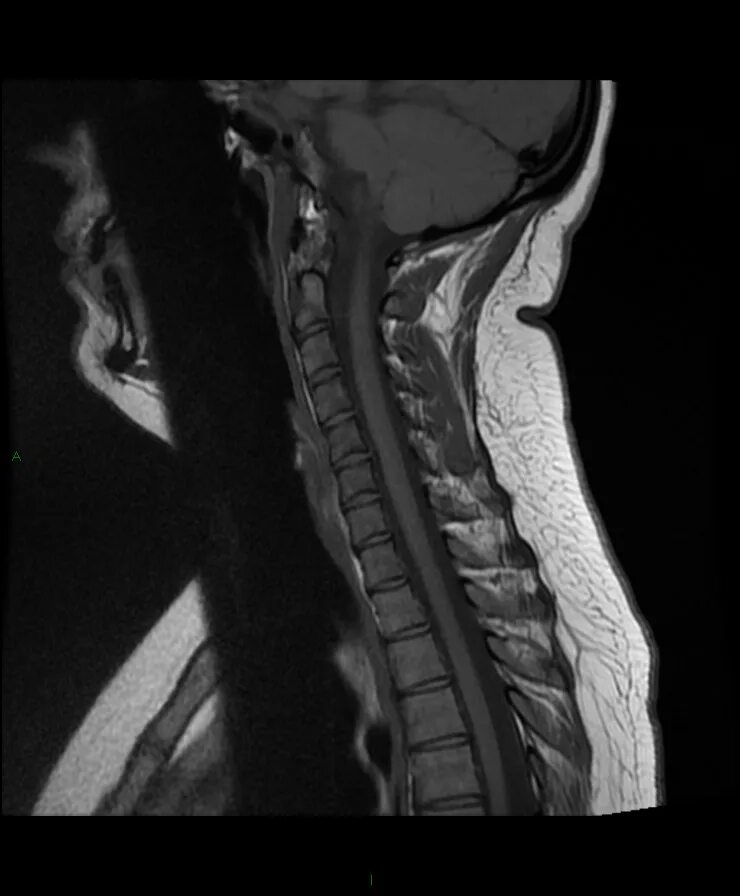

Spine mri